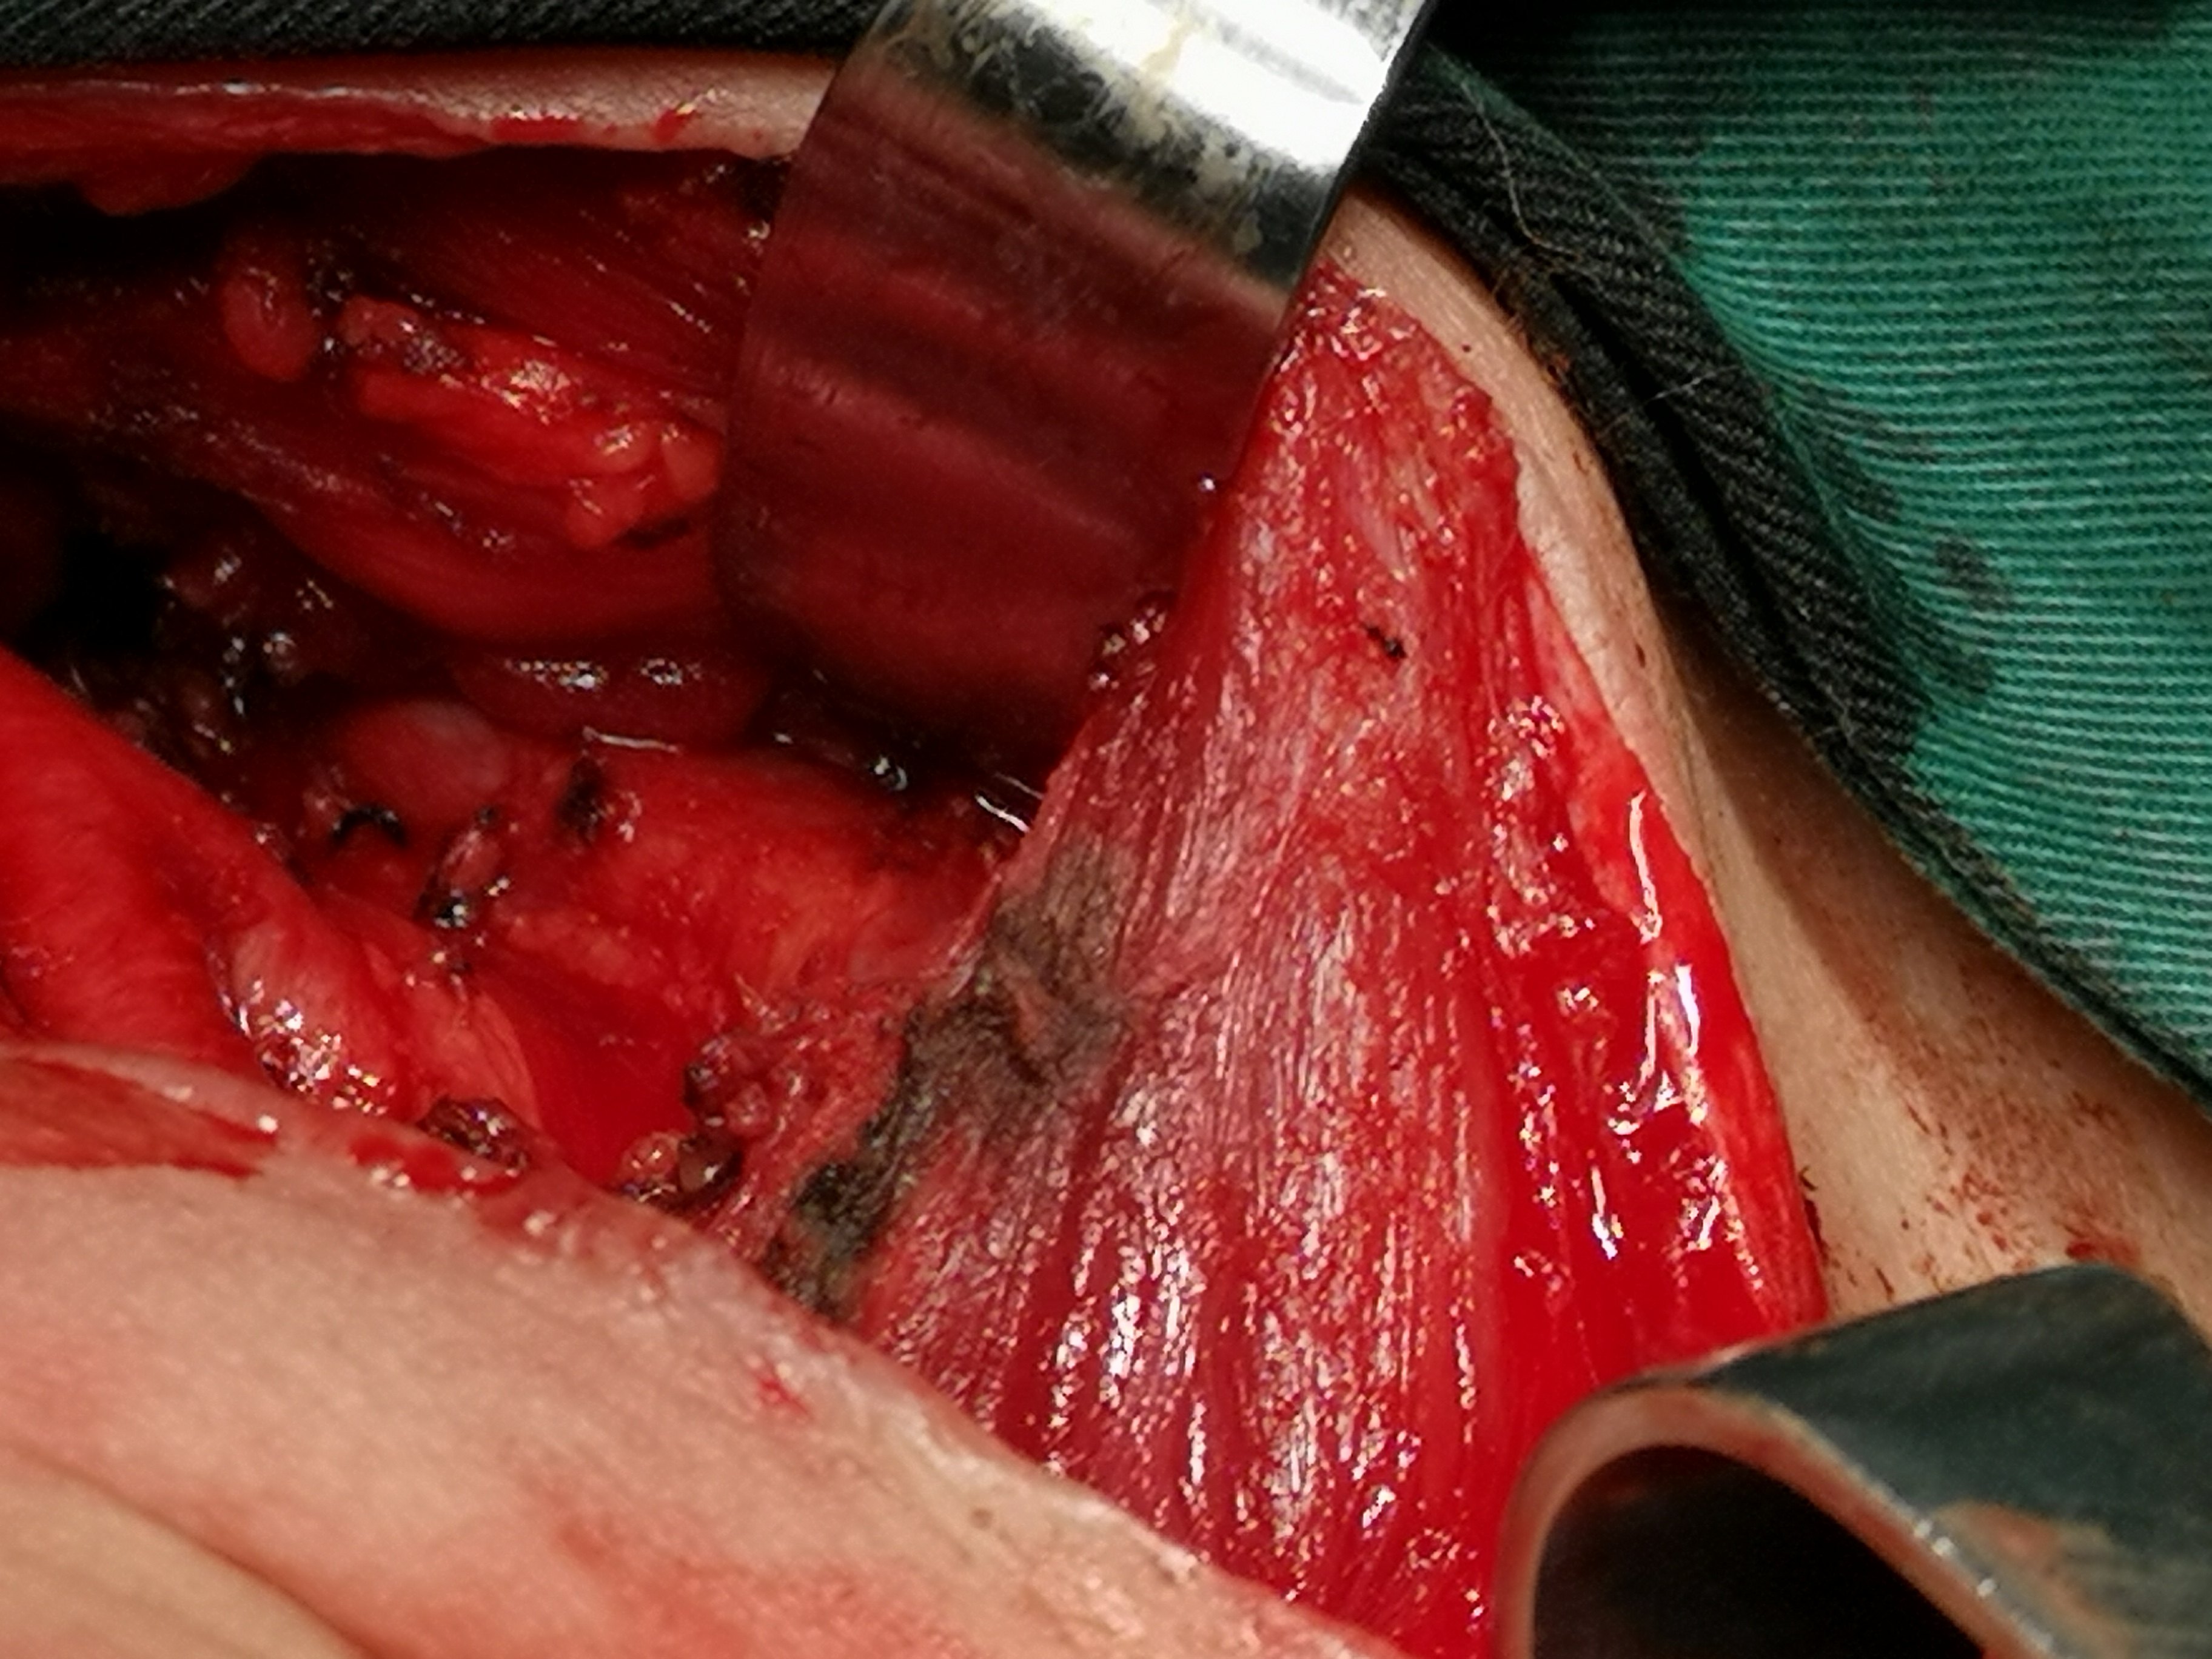

甲状腺癌再次手术

病例2 右2,右4R区,左6区残留,颈部切口清扫,未开胸